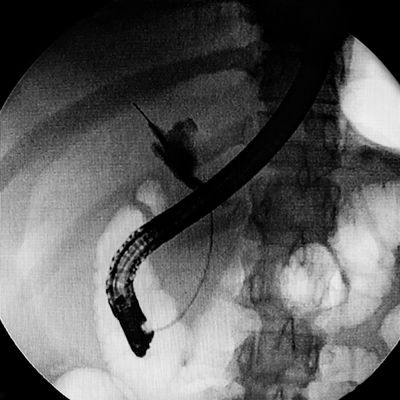

ERCP (endoscopic retrograde cholangiopancreatography) is a procedure to diagnose and treat problems in the gallbladder, bile ducts, and pancreas. It combines endoscopy and fluoroscopy.

In this procedure, the endocopist inserts a long, thin, hollow tube called an endoscope down a person’s throat and into their duodenum, or small intestine. The endoscope has a light and a side viewing lens. Once the doctor positions the hollow endoscope correctly, they pass another long narrow tube called a catheter into the endoscope. They use the catheter to deliver dye to the affected area to develop X-ray images.

With fluoroscopy, doctors get a continuous flow of X-ray images which helps them